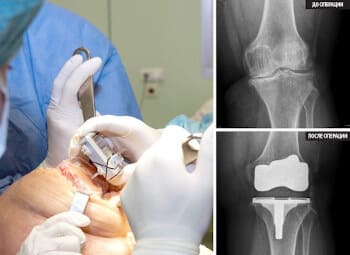

জয়েন্ট স্টেন্টিং খুব ব্যয়বহুল, এবং একটি খুব গুরুতর অপারেশন।

হাঁটু এন্ডোপ্রোস্টেসিস, ছবি